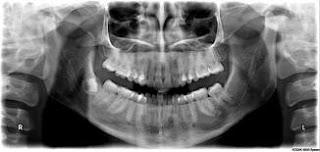

Panoramica dentale

esegue tramite radiografia e che permette di mostrare in maniera precisa e

approfondita i denti, l’arcata superiore e inferiore e tutta la mandibola in

generale.

la cura dentaria. La panoramica dentale

si ottiene utilizzando uno specifico strumento che prende il nome di ortopantomografo, costituito da un

braccio orizzontale nel quale deve essere posizionata la nuca del paziente. In

questo modo i raggi X attraversano

le diverse componenti dentarie e proiettano l’immagine su di una pellicola.

Tutto il processo dura solo qualche minuto.